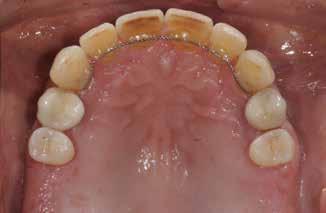

Patienttilfælde 1 (Fig. 1) er en 37-årig kvinde, henvist efter succesfuld behandling af stadie 3-parodontitis. Der er nu sundt

Før behandling

parodontium, ingen pocher over 4 mm, og både blødnings- og plakindeks er under 10 %. Patienten er motiveret for ortodontisk behandling, da hendes tænder er vandret over tid, delvist som følge af reduceret parodontium.

Der ses anterior trangstilling i begge kæber og overerupterede 1+1 og 2,1-1,2, hvilket resulterer i dybt bid med 2- tæt på ganepåbidning. Der er normale sidetandsrelationer, men der ses 5 mm horisontalt overbid (HOB) og 7 mm vertikalt

overbid (VOB). Papillen mellem 1+1 er betydeligt reduceret pga. fæstetab, og de mesialt kippede 1+1 har resulteret i en ”dark triangle”. Den facioorale funktion er for nuværende i.a. Panoramarøntgen (Fig. 1, I) viser marginalt knogletab i begge kæber og fravær af 8,7+7,8 og 8,7-8.

Objektivt anbefales behandling af det dybe bid, som ubehandlet forventes at forværres yderligere over tid. Patienten har ønske om behandling med æstetisk ortodontisk apparatur, alignere, og det vurderes muligt at behandle malokklusionen med alignere. Dog anbefales det generelt, at alignere undgås eller benyttes med væsentlige modifikationer af alignerens retention ved tandmobilitet, da dette ellers kan medføre jiggling, når aligneren tages af og på mange gange dagligt. På den anden side er der nogen evidens for, at alignerbehandling er associeret med bedre renhold og parodontal sundhed sammenlignet med fast apparatur (16).